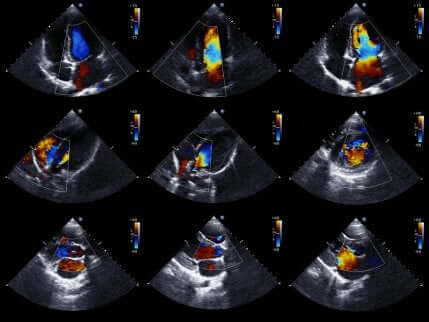

Som det sidste giver ekkokardiogrammer eller hjertesonogrammer medicinske fagfolk mulighed for at studere hjertet mere detaljeret.

Ekkokardiogrammet er en meget populær medicinsk test. Dette skyldes, at den giver bevægelige billeder af hjertet. Således kan den evaluere status for hjertets kamre og deres bevægelser for at bekræfte eller udelukke iskæmi.

Derudover evaluerer den også hjertestørrelse og styrke og tilstanden af væggene i hjertets kamre. Generelt er det en ikke-invasiv test, der ikke indebærer nogen risiko for patienten. Dette skyldes, at den bruger ultralyd til at få hjertebilleder.

Hvis lægen bruger denne test, udelukker fraværet af bevægelsesforstyrrelser i hjertevæggen tilstedeværelsen af iskæmi. Når alt kommer til alt, er eksistensen af bevægelsesforstyrrelser ikke unik for akut koronart syndrom. Af den grund skal testresultaterne og symptomerne vurderes i sammenhæng.